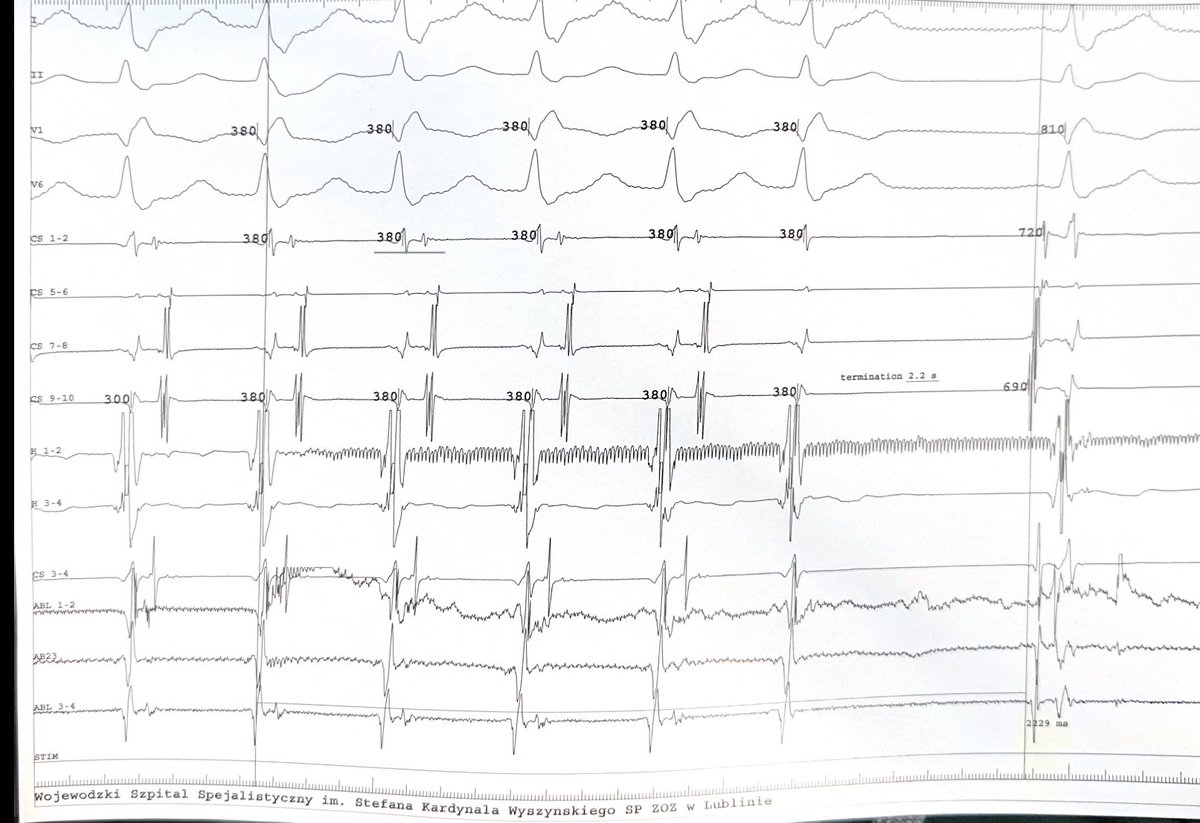

A 62 YOF with a history of surgical correction of partial AVSD and mitral cleft, after CTI ablation+scar homogenization. AT with CL 260ms and prox->distal activation on CS. Here is the initial RA map.

What do you do next?

Termination of atypical flutter along anterior LA isthmus identified with crunchy electrograms (2nd post). Satisfying mechanistically and knowing ablation was the right choice.